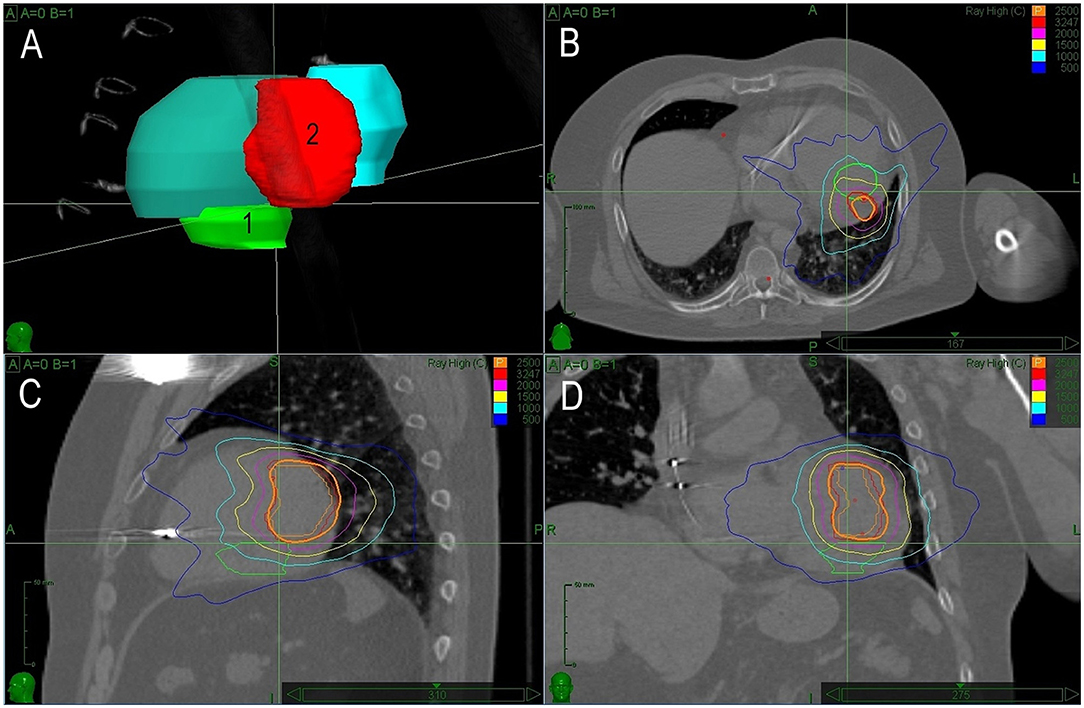

The first case was reported recently in detail as a case report, illustrating the need for precision in planned target volume (PTV) determination (20). Briefly, a 66-year-old man with a history of coronary artery bypass graft surgery and primary prophylactic ICD implant (left ventricular ejection fraction of 35%) underwent catheter ablation for recurrences of slow VT. Clinical VT originated from a small reentrant circuit located intramurally and/or epicardially below the base of the posteromedial papillary muscle. Despite multiple endocardial ablation attempts, VT remained inducible and an attempt for percutaneous epicardial approach failed because of severe adhesions from previous cardiac surgery. The first SBRT session was planned based on a visual alignment of the presumed origin of VT from electroanatomical maps and CT images. A single fraction of 25Gy was delivered. For recurrences of VT episodes of the same ECG morphology, the patient underwent the second electrophysiology study and remapping 14 months later. Based on the electroanatomical mapping, the low voltage area caused by the previous SBRT was adjacent to the site of the earliest endocardial activity during VT. Additional RF ablation failed again to prevent the inducibility of VT and we used a newly developed co-registration method for the precise targeting of the SBR (20). Detailed maps were presented in a previously published case report (20). Briefly, there was only a small bipolar low voltage area after the first SBRT which was adjacent to the true exit of VT. Precise co-registration of the target in the second SBRT allowed to establish a smaller PTV amounting to 18 ml, including an additional 3 mm margin. The dice overlap of previous and new PTV was 0.68. The second session was performed 19 months after the first one. The same dose of 25 Gy was delivered (Figure 1). After transient early recurrences of slow VT, arrhythmias gradually disappeared within 3 months and the patient became arrhythmia-free for 32 months. No adverse effect of SBRT was observed during this period.

Figure 1. A treatment plan for Case 1. (A) 3D reconstruction of planned treatment volumes for the first (1) and second (2) radiotherapy. (B–D) Depict sagittal, coronal, and axial views with isodose lines for both sessions of radiotherapy (green line shows target volume for the first and red for the second session). In this case, there is a significant overlap of both treatment volumes caused by inaccuracy in the planning of the first session.